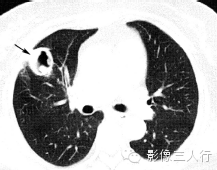

| 肺脓肿(图1) | 肺结核空洞(图2) | 癌性空洞(图3) | |

| 空洞形态 | 洞壁厚、模糊,内壁较光滑,内多见液平面 | 洞壁薄、内壁较光整,周围常有卫星灶 | 洞壁厚,多呈偏心性增厚,内壁常呈结节状 |

(B)平扫肺窗